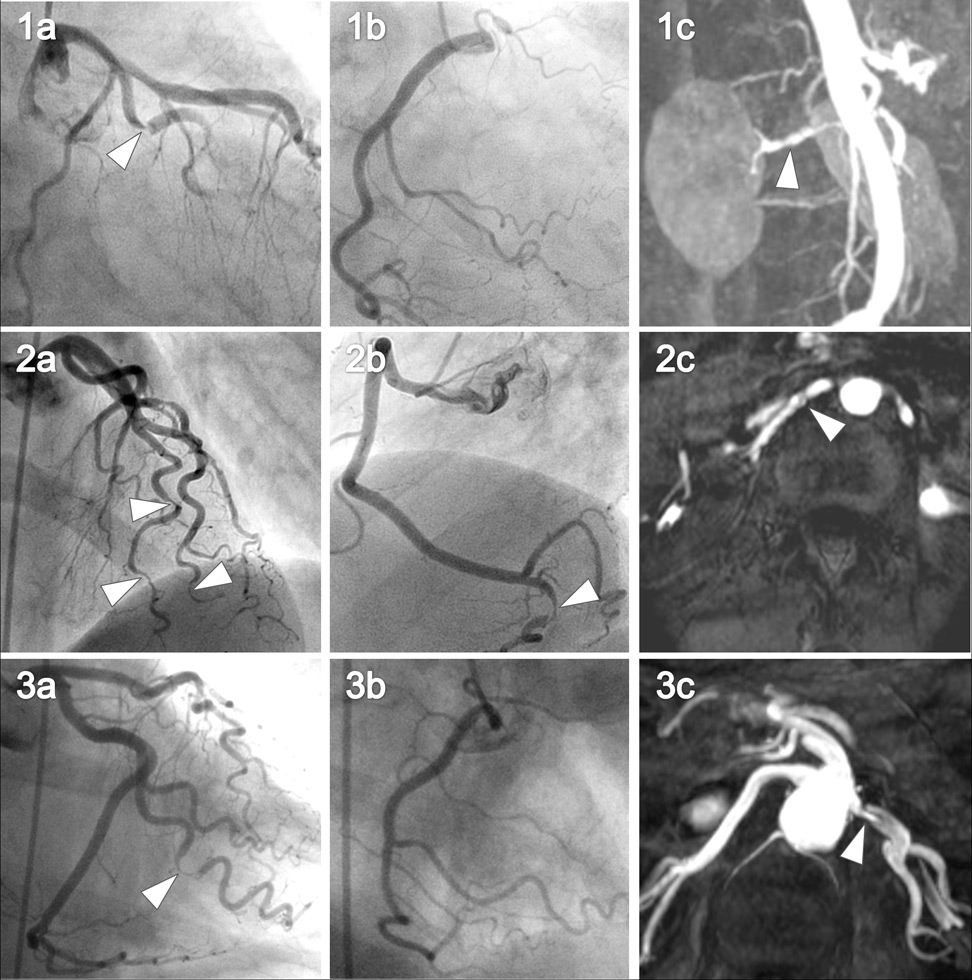

Figure 3

Coronary angiography and renal MR angiography of the 3 women with renal artery abnormalities.

The left (images 1a, 1b, 1c) and right coronary (images 2a, 2b, 2c) angiography is shown for all three patients with the corresponding renal artery abnormalities (images 3a, 3b, 3c). Arrows in images 1a–c and 2a–c point at spontaneous coronary artery dissections. Arrows in images 3a–c point at renal artery fibromuscular dysplasia (3a, 3b) and renal artery dissection (3c).

MRA and duplex sonography were performed after a median of 1,036 (range: 78–1938) days after the SCAD. Abnormalities of the renal arteries were found in 3/12 (25%, table 2), all were women. Two patients showed a transverse striated “string of beads” angiographic appearance of the renal artery, consistent with fibromuscular dysplasia (fig. 3, patients 1 and 2). In 1 patient an ostial dissection of the left renal artery without a significant stenosis was found (fig. 3, patient 3). MRA of the extracranial arteries was normal in all patients.

Pathologic findings of the renal artery were found in 2 patients (table 2). A <70% stenosis of the middle part (peak systolic velocity of 210 cm/s) of the right renal artery was observed in a 63 year old woman and a <50% stenosis (peak systolic velocity of 130 cm/s) in a 40 year old woman (fig. 3, patients 1 and 2). Discrete wall thickening of the carotid bulb was found in 3 patients, all other carotid arteries were normal. Intima media thickness was 0.54 ± 0.15 on the right side and 0.55 ± 0.12 on the left side. No dissections were identified by Duplex sonography.